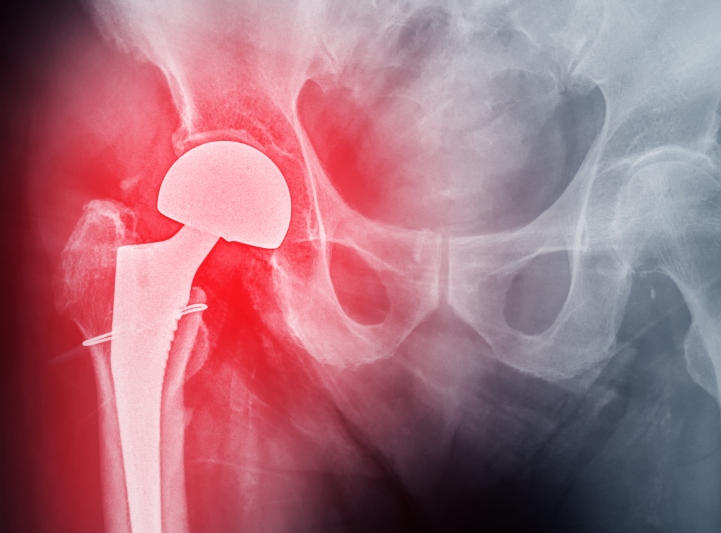

髋关节是人体负重的“核心枢纽”,而股骨头坏死作为中老年人高发…… 【详情】

股骨头坏死前期,骨骼尚未严重塌陷,但髋部疼痛、活动受限等症状已悄…… 【详情】